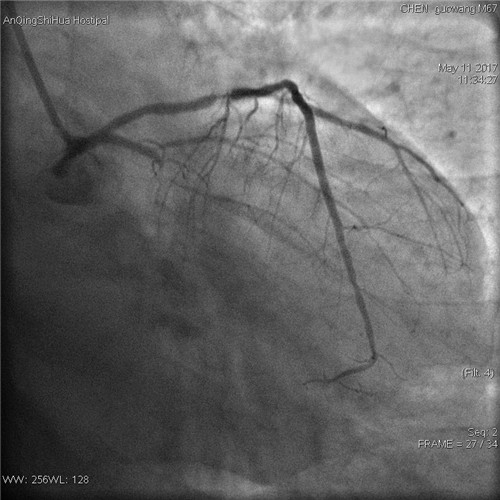

術(shù)前 回旋支完全閉塞